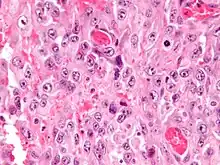

| Micrograph of an epithelioid sarcoma. H&E stain. | |

Histologically, epithelioid sarcoma forms nodules with central necrosis surrounded by bland, polygonal cells with eosinophilic cytoplasm and peripheral spindling.[3] Epithelioid sarcomas typically express vimentin, cytokeratins, epithelial membrane antigen, and CD34, whereas they are usually negative for S100, desmin, and FLI1 (FLI-1).[3] They characteristically lack the protein INI1 (see below). Epithelioid sarcomas typically stain positive for CA125.[4]